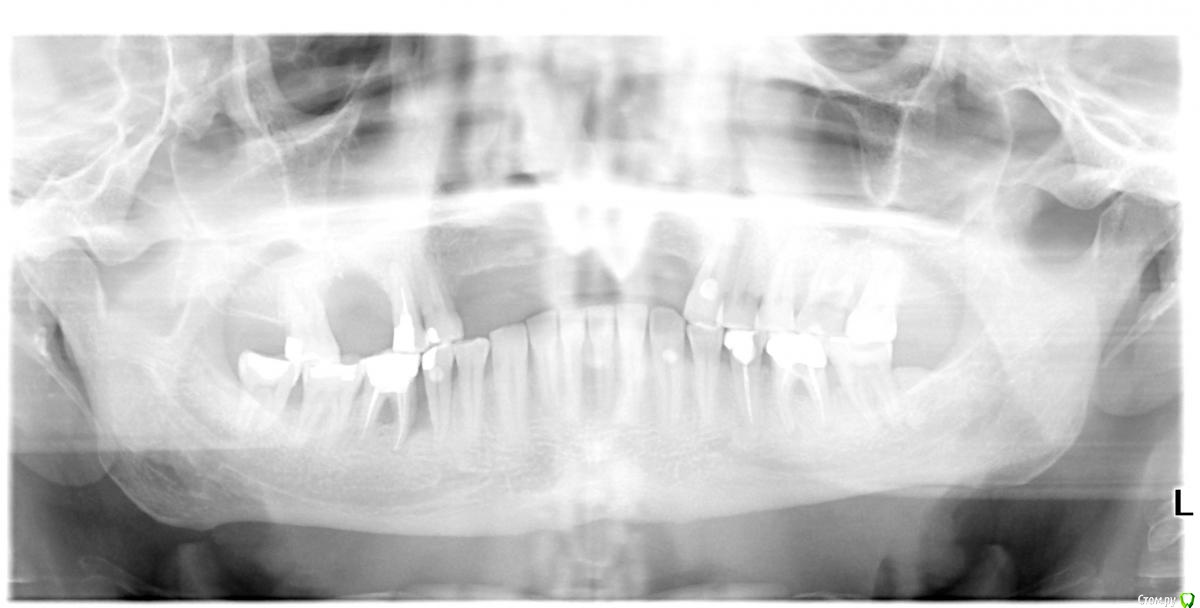

Собственно ситуация такая. Фронтальные зубы сверху были потеряны в результате серьезной травмы,  ! Фактически полное отсутствие костной ткани в области фронтальных зубов и по толщине и по высоте. Пациент ходит с чс протезом и хочет нечто несъемное.

Интересует как лучше это сделать при таких объемных дефектах.  Мои мысли первым этапом сосидж, потом 4 импланта. Но как быть с временным протезированием?

какой тут сосидж? Он для фронтального отдела не очень то годится.

Тут нужна вертикальная аугментация с каркасной мембраной.